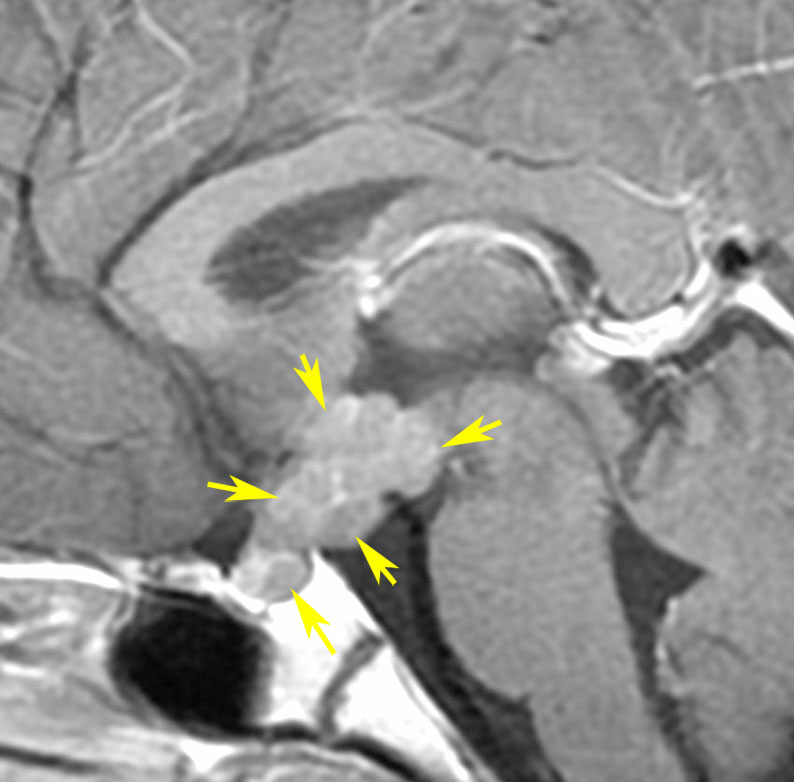

放射線が外れやすい部位は再発源となります

側脳室先端(前角,後角,側頭角,閂),下垂体と大脳基底核に放射線が入らないとその部位から再発します。

再発ジャーミノーマの画像です。延髄背側の閂 ovexという部位に再発しています。

このパターンはとても多いです。なぜかというと,全脳室照射の時に,第4脳室下端のovexの上衣 ependyum を照射野に入れない放射線治療医の先生がいるからです。放射線科の先生にもちょっとした知識が必要なのです。

これは再治療で腫瘍が消えても不可逆的な重症の延髄障害を残してしまいます。